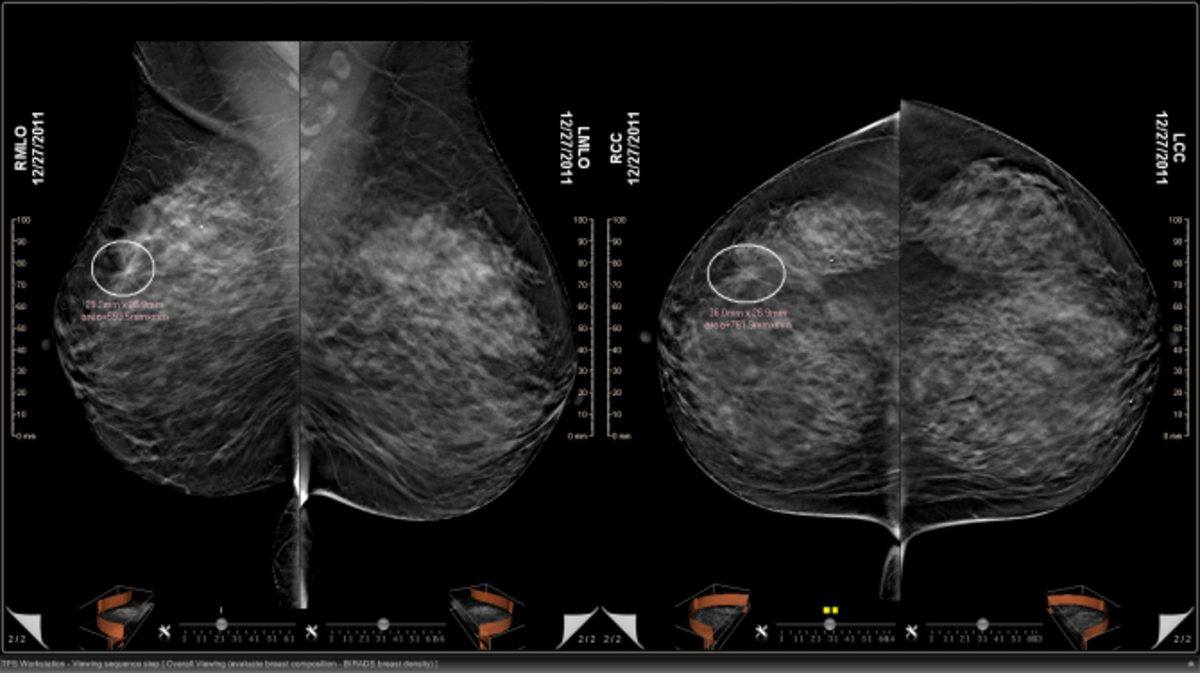

Με την τεχνολογία της τομοσύνθεσης, (Digital Breast Tomosynthesis) ο μαστός απεικονίζεται με πολλαπλές λεπτές τομές του ενός χιλιοστού, στοιχείο που δεν επιτρέπει σε τίποτα να διαφύγει του ελέγχου. «Με αυτόν τον τρόπο», τονίζει ο κ. Μαλακάσης, «η μαστογραφία αποδεικνύεται η πιο αξιόπιστη εξέταση για τη γυναίκα, ακόμα και στις περιπτώσεις πολύ πυκνών μαστών, οι οποίοι ‘’ευθύνονται’’ για το συχνό φαινόμενο της ψευδούς αρνητικής διάγνωσης σε πρώιμο στάδιο».

Υπενθυμίζεται ότι η τομοσύνθεση, είναι μία καινούργια τρισδιάστατη (3D) τεχνολογία απεικόνισης μαστού, με υψηλότερη διαγνωστική ακρίβεια στη διάγνωση των παθήσεων του μαστού, έναντι της κλασικής μαστογραφίας, καθώς έχει τη δυνατότητα να ξεχωρίζει τα ύποπτα ευρήματα, τα οποία οδηγούν στην ανεύρεση και της πλέον μικρής βλάβης.